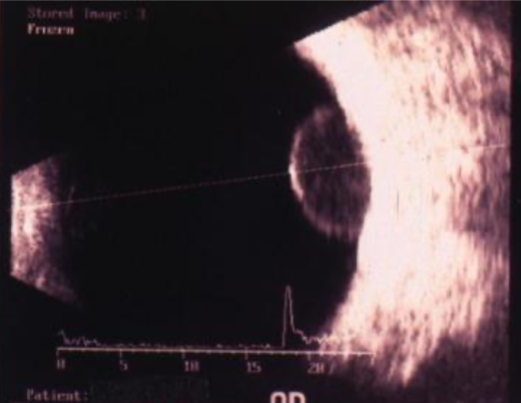

ultrasound

low-medium reflectivity, excavation of underlying uveal tissue, shadowing of subjacent soft tissues, internal vascularity, acoustic hollowing

what do intraocular melanomas show on B-scan?

acoustic hollowing

characteristic finding on B-scan of an intraocular melanoma; acoustic quiet zone at the base of the tumor